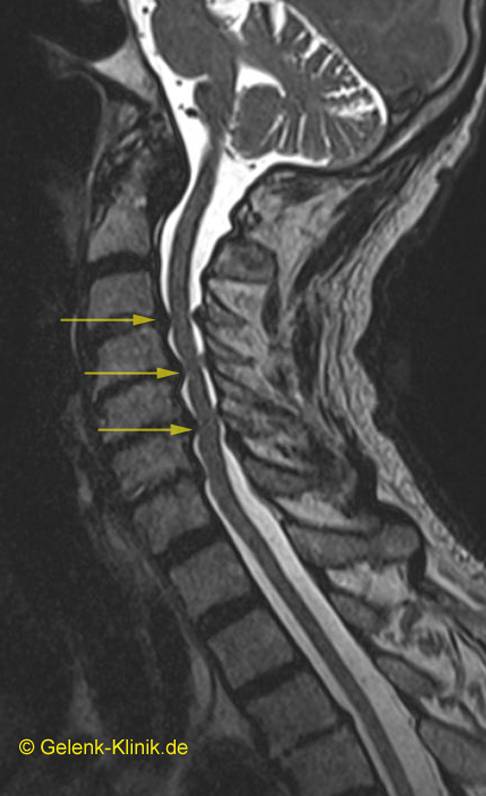

Zusätzlich zur klinischen und neurologischen Untersuchung zieht der Rückenspezialist bildgebende Verfahren heran. Unerlässlich zum Nachweis einer Wirbelkanalstenose ist – neben der obligatorischen Röntgenuntersuchung – eine Magnetresonanztomografie (MRT).

Die MRT zeigt z. B. die einengenden Spondylophyten oder die Vorwölbung einer höhenverminderten, dehydrierten Bandscheibe in den Spinalkanal hinein. Manchmal sind auch mehrere Stenosen sichtbar. Nur durch genaue Abstimmung der radiologischen Befunde mit den Ergebnissen der neurologischen Untersuchung und der Beschwerden des Patienten lässt sich die klinische Relevanz der sichtbaren Engstellen deuten.